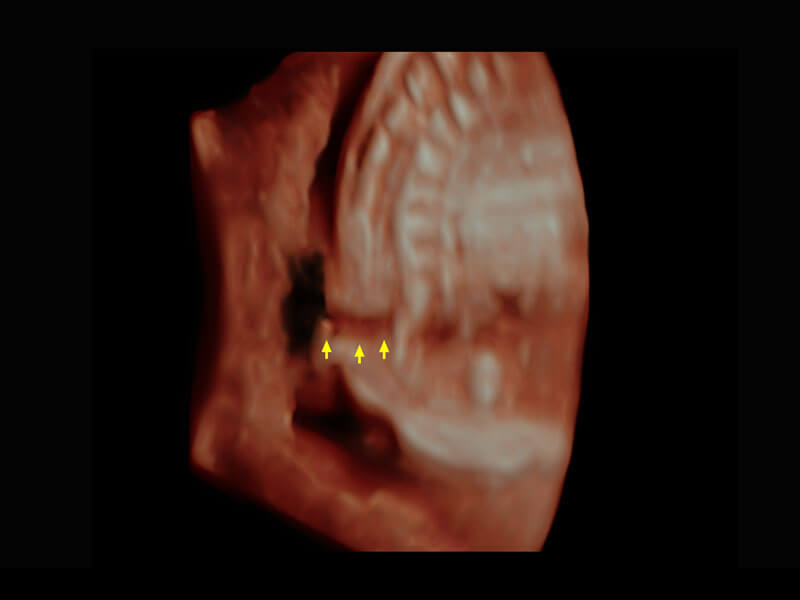

腔内三维-宫内节育器

腔内三维-光影成像

P60搭载一系列胎儿心脏成像技术,实现精细的胎儿心脏评估。

右室双出口

胎心容积成像